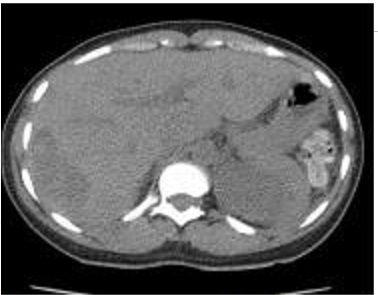

Image TDM du foie en coupe

axiale ( avec contrast iode intra veineuse ) . |